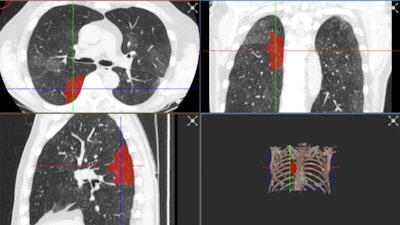

The best AI platforms have a wide range of labeling and segmentation options so that images can be presented correctly. With the RVAI platform from Robovision, the margins of the opacities in the lung are automatically identified by the "adaptive" brush tool. The lesions or abnormalities are simultaneously segmented in three different planes. In this figure, not all visible opacities have been segmented yet. Images courtesy of Dr. Erik Ranschaert, PhD.The added difficulty of COVID-19 lung abnormalities is they can be subtle and difficult to differentiate from other conditions. Last week, for example, Ranschaert and his colleagues at the Elisabeth-TweeSteden Hospital in Tilburg, the Netherlands, treated a patient with a pneumocystis carinii pneumonia infection. As in COVID-19 cases, this infection can give similar opacification on both sides of the lungs, so it requires great care and can be misdiagnosed, he pointed out.